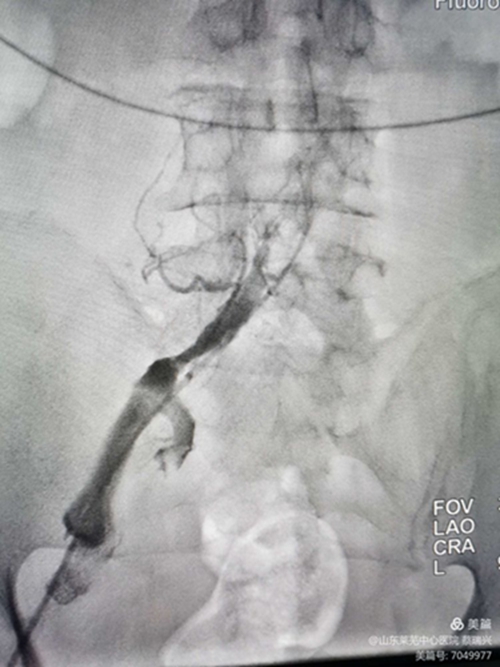

男性,81歲,左下肢腫脹4天入院,行走不至百米,疼痛,便要休息,嚴(yán)重功能障礙。左下肢I(xiàn)II度水腫,脹力高。腳踝部有淤血斑。彩超示,左下肢深靜脈諸段屬支血流通暢,速度慢。髂總靜脈觀察不清。認(rèn)為還是髂總有問題,行造影。取左腘靜脈入路,造影證實(shí)左髂總靜脈閉塞,開通后留置溶栓導(dǎo)管4天。給予左髂總靜脈支架成形術(shù)。溶栓導(dǎo)管造影證實(shí),左髂總?cè)杂兄囟泉M窄,血流不暢,易再閉。

閉塞前改變